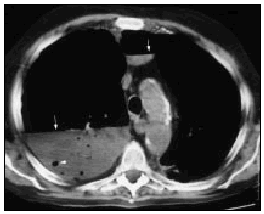

Varón de 60 años, diabético y con insuficiencia respiratoria crónica por enfisema pulmonar que ingresa por una neumonía en el lóbulo medio derecho. Se inició tratamiento con broncodilatadores inhalados, una cefalosporina de tercera generación y un macrólido, con mejoría inicial. En la tercera semana, ante la persistencia de cuadro febril, se realizó una radiografía de tórax (fig. 1) en la que se observa un infiltrado en el pulmón derecho de gran tamaño y con nivel hidroaéreo, por lo que se le añadió un antibiótico anaerobicida. En una TC torácica se observaba la lesión ya conocida (fig. 2. flecha izquierda) y otra pequeña imagen redondeada, con nivel hidroaéreo en su interior, en el espacio prevascular (fig. 2. flecha derecha). El fluido contenido en la lesión mayor era más denso que el agua y tenía burbujas de gas en su interior (fig. 2 punta de flecha). En un cultivo de esputo se cultivó Pseudomonas aeruginosa multisensible. Tras un acceso de tos, en una nueva radiografía de tórax (fig. 3) desaparece el infiltrado derecho, diseminándose la infección pulmonar, falleciendo el paciente días después en situación de shock séptico. Se estableció el siguiente diagnóstico: bullas pulmonares infectadas; bronconeumonía bilateral por P. aeruginosa.

Fig. 1.